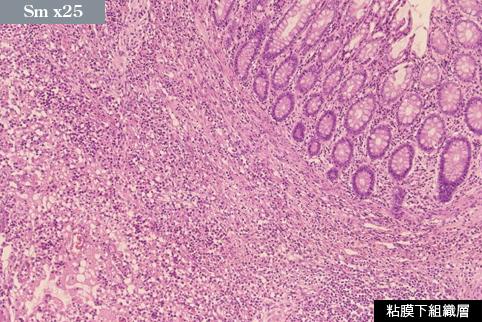

A case of mesenteric panniculitis that induced multiple stenosis of the large intestine.

Fukuoka Pref., MUNAKATA MEDICAL ASSOCIATION (Dr.Miyasaka , Dr.Yoshida)

Inflammatory or ulcerative disease / lesions/Others

Large intestine(Colon)/More than one of the above

Histology